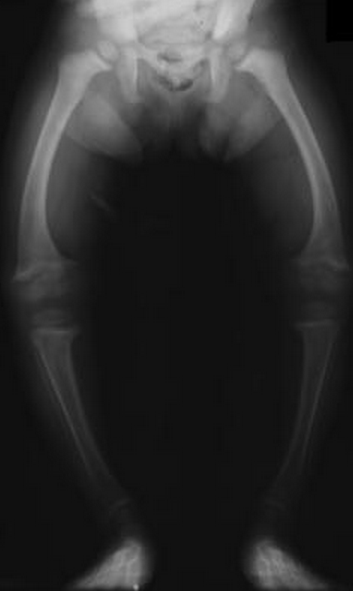

An 8 year old child comes to the ER, appear malnourished with bowing bones as seen in the x-ray below. What is this child likely deficient in and how is this contributing to his symptoms?

This poor kid has Rickets (osteomalacia in adults). This is a result of vitamin D deficiency which results in a decrease in serum calcium. The parathyroid senses this and stimulates bone resorption. This results in an overall decrease in mineralization of osteoid and the bones bow outwards.